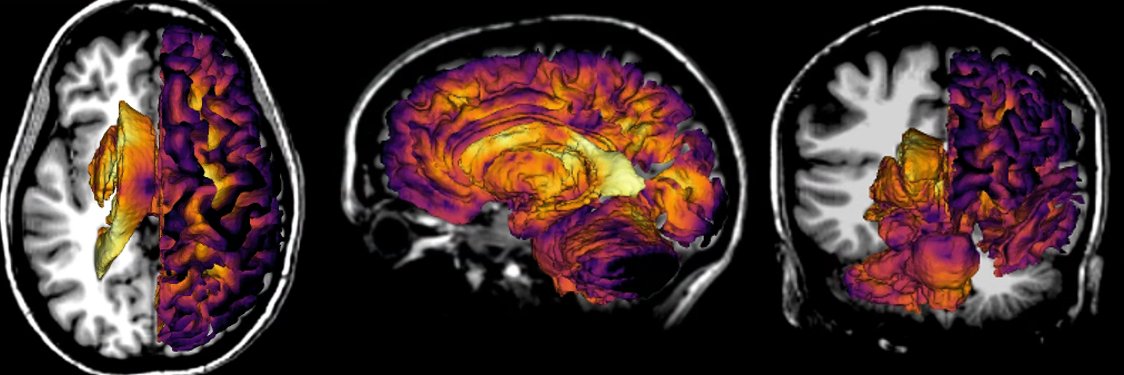

WORKSHOP WEDNESDAY: Save the date for the ISMRM Workshop on MR Spectroscopy! ow.ly/9jcv50RZaEJ Abstract Submission Deadline: 19 July 2024 Learn about the MRSI Data Processing Challenge: bsoher.github.io/FittingChallen… Registration coming soon! #ISMRM #ISMRT #MRI #MagneticResonance